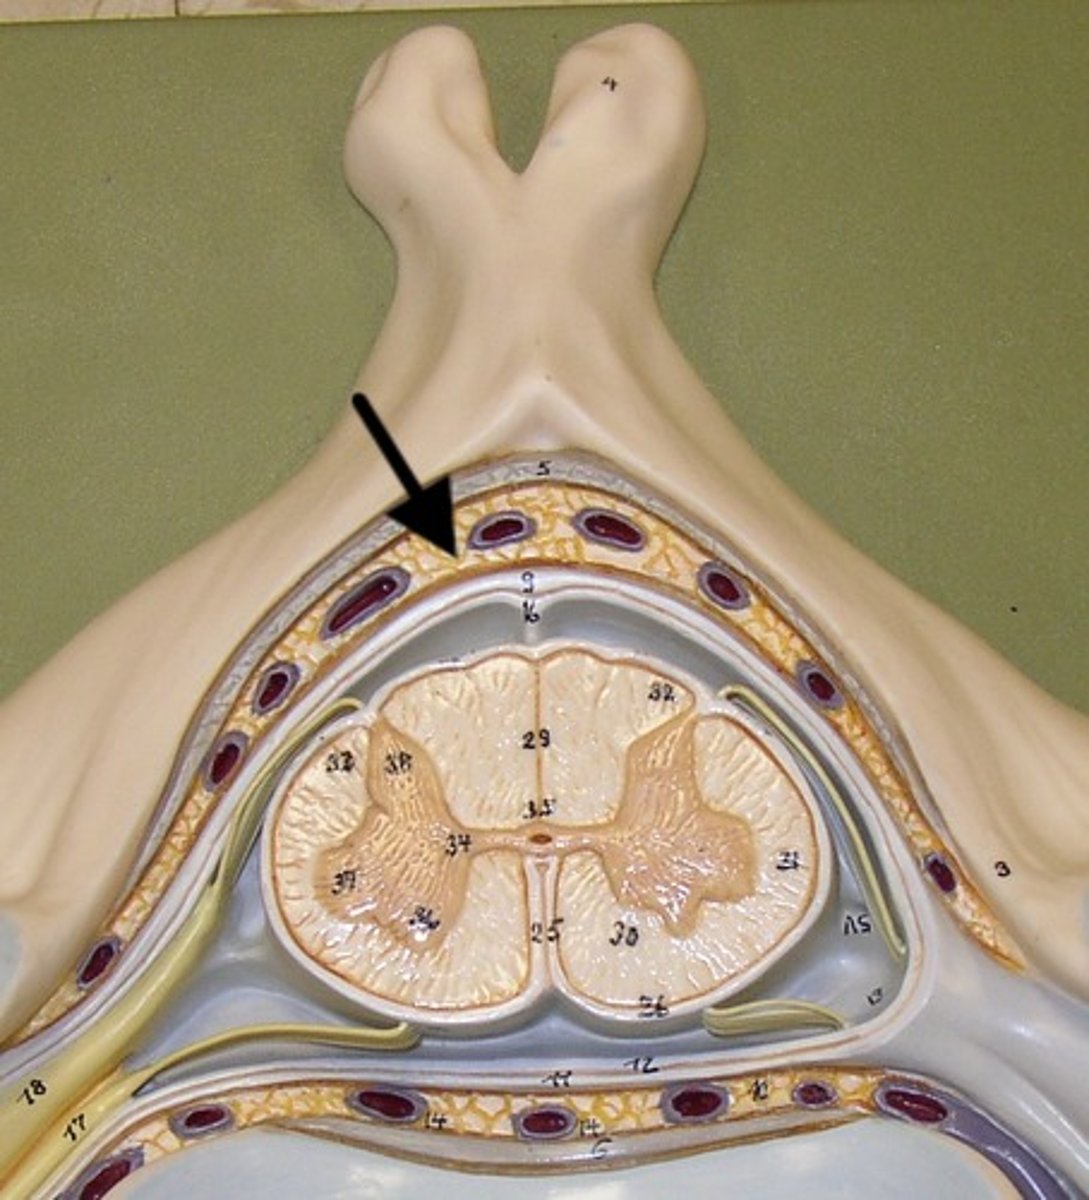

anterior (ventral) root (of spinal cord)

central canal (of spinal cord)

gray matter (of spinal cord)

posterior median sulcus

anterior median fissure

cauda equina

dorsal root ganglion (spinal)

posterior (dorsal) root (of spinal cord)

spinal nerve

white matter (of spinal cord)

arachnoid mater

dura mater

denticulate ligament

pia mater

subdural space

epidural space

subarachnoid space